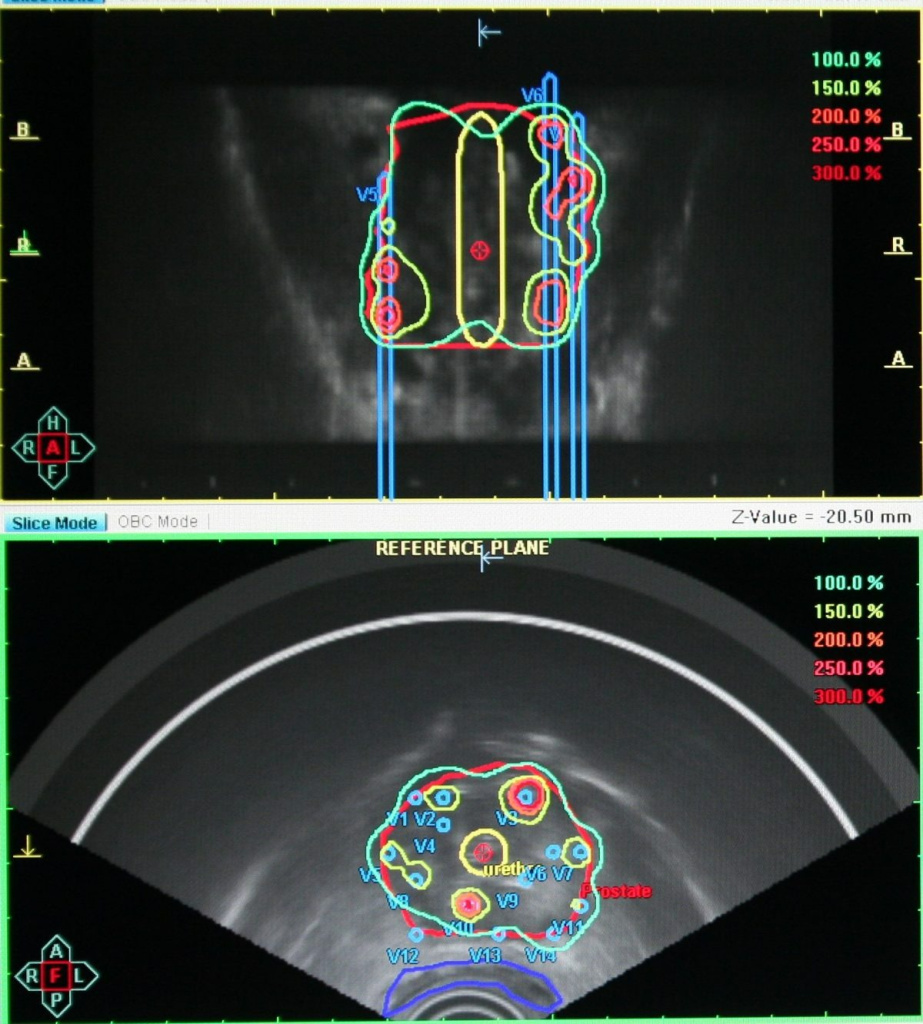

Брахитерапия — один из самых востребованных радиологических методов, так называют облучение с высокой избирательностью подведения дозы.

Его основная особенность — предстательная железа, пораженная опухолевым процессом, облучается «изнутри», источники излучения вводятся в железу.

Это позволяет бороться с опухолью высокими дозами (100Гр-140Гр и выше), избегая повышенного риска лучевого поражения здоровых тканей.